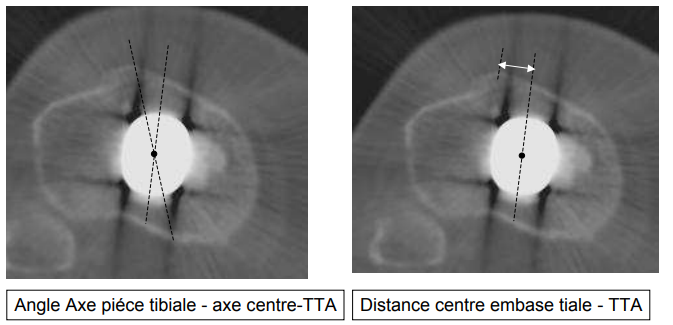

Evaluation de la pièce tibiale

- Angle Axe pièce Tibiale - centre TTA

- Distance centre embase tibiale - TTA